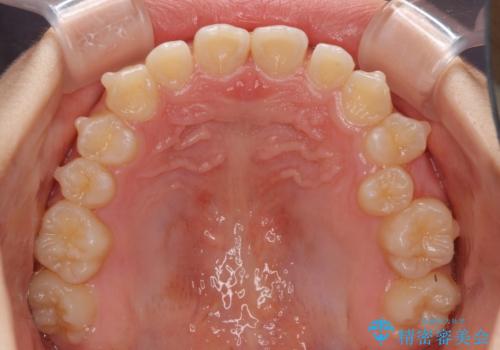

- 小児矯正の頃から診察を行っている患者様です。

上顎骨の幅が下顎骨よりも小さいので、拡大装置により骨幅を広げて上下関係を改善し、その後インビザラインにて歯並びを整えることとしました。

上下の骨幅を改善したことで、スムーズに歯列矯正を行うことができました。